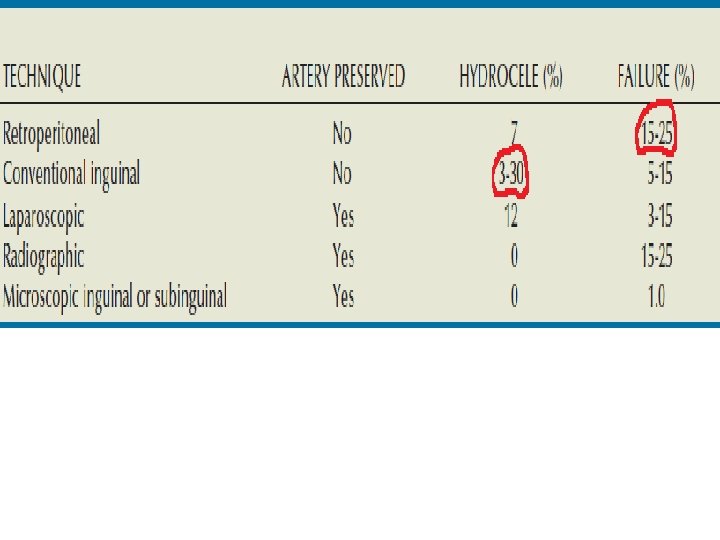

Methods Of Surgical Repair Ø Scrotal Approach ØRetroperitoneal approaches (Open or Laparoscopic) Ø Inguinal Approach Ø Sub-Inguinal Approach Ø Radiographic Occlusion Techniques (Embolization)

Ø Scrotal Approach The very 1 st approach for varicocele repair employed in the early 1900 s. Involves mass ligation & Excision of the varicosed veins. Not preferred practically due to the high incidence of testicular artery injury with subsequent impairment of the testicular blood supply, testicular atrophy & more impaired spermatogenesis & fertility.

Retroperitoneal(Palomo)Approach Incision at the level of the internal ring near to the Anterior Superior Iliac Spine. Exposure of the Internal Spermatic Artery & Vein retroperitoneaelly near the ureter where only one or two large veins are present & the testicular artery is not yet branched & so easy to separate. A disadvantage of a retroperitoneal approach is the high incidence of varicocele recurrence, especially in children and adolescents, when the testicular artery is intentionally preserved.

Laparoscopic Approach It is an essence retroperitoneal approach with similar advantages & disadvantages, including rate of recurrence. The internal spermatic veins are ligated with the laparoscope at the same level as the retroperitoneal approach with preservation of the testicular artery. The potential complications of laparoscopic varicocelectomy (injury to bowel, vessels or viscera, air embolism, peritonitis). Laparoscopic Approach is a reasonable alternative for the repair of bilateral varicoceles.

The Inguinal Approach can be used in almost any patient It allows for mobilization of the cord, identification of any large veins within the cremasteric muscle. identification of veins perforating the posterior inguinal canal that might be contributing to the varicocele. Conventional inguinal operations are associated with an incidence of postoperative hydrocele formation varying from 3% to 15%.

Complications of Varicocelectomy Hydrocele the most common complication reported after nonmicroscopic varicocelectomy. The incidence of this complication varies from 3% to 33%, with an average incidence of about 7%. hydrocele formation after varicocelectomy is due to lymphatic obstruction. Use of magnification to identify and preserve lymphatics can virtually eliminate the risk of hydrocele formation.

Testicular Artery Injury The diameter of the testicular artery in humans is 1. 0 to 1. 5 mm The testicular artery supplies 2/3 of the testicular blood supply, and the vasal and cremasteric arteries supply the 1/3. Injury or ligation of the testicular artery carries with it the risk of testicular atrophy and/or impaired spermatogenesis. (which is less likely to occur in children due to compensatory neovascularization). The Use of Magnification & Micro-Doppler helps good identification & Preservation of the testicular artery.

Varicocele Recurrence The incidence of recurrence after varicocele repair varies from 0. 6% to 45%. Recurrence is mostly associated with: 1). Pediatric Varicocele 2). Non-Magnified Operations 3). Retro-peritoneal approaches (that misses the parallel inguinal collaterals.